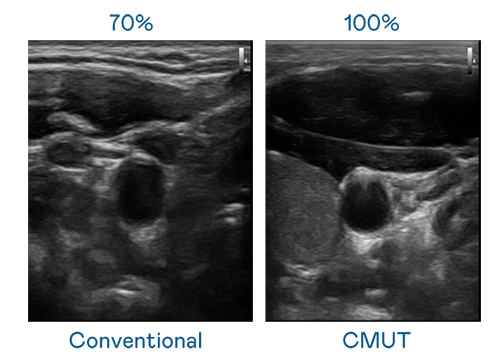

CMUT 技术是一种用电容式微机电元件来产生超音波讯号的技术。与传统 PZT 压电式技术相比,CMUT 频宽增加 30%,更宽频的超音波讯号让影像解析度大幅提升,是实现高影像品质医疗超音波扫描、促进精准医疗发展的关键技术。

超音波影像的解析度高低,首先取决于探头能发出的讯号频宽。918搏天堂 CMUT 可提供高清晰的超音波讯号,提供高频宽、高灵敏度、影像纹理细节更高的超音波影像,协助医护人员缩短影像判读时间及利用精准的医疗影像进行诊断。